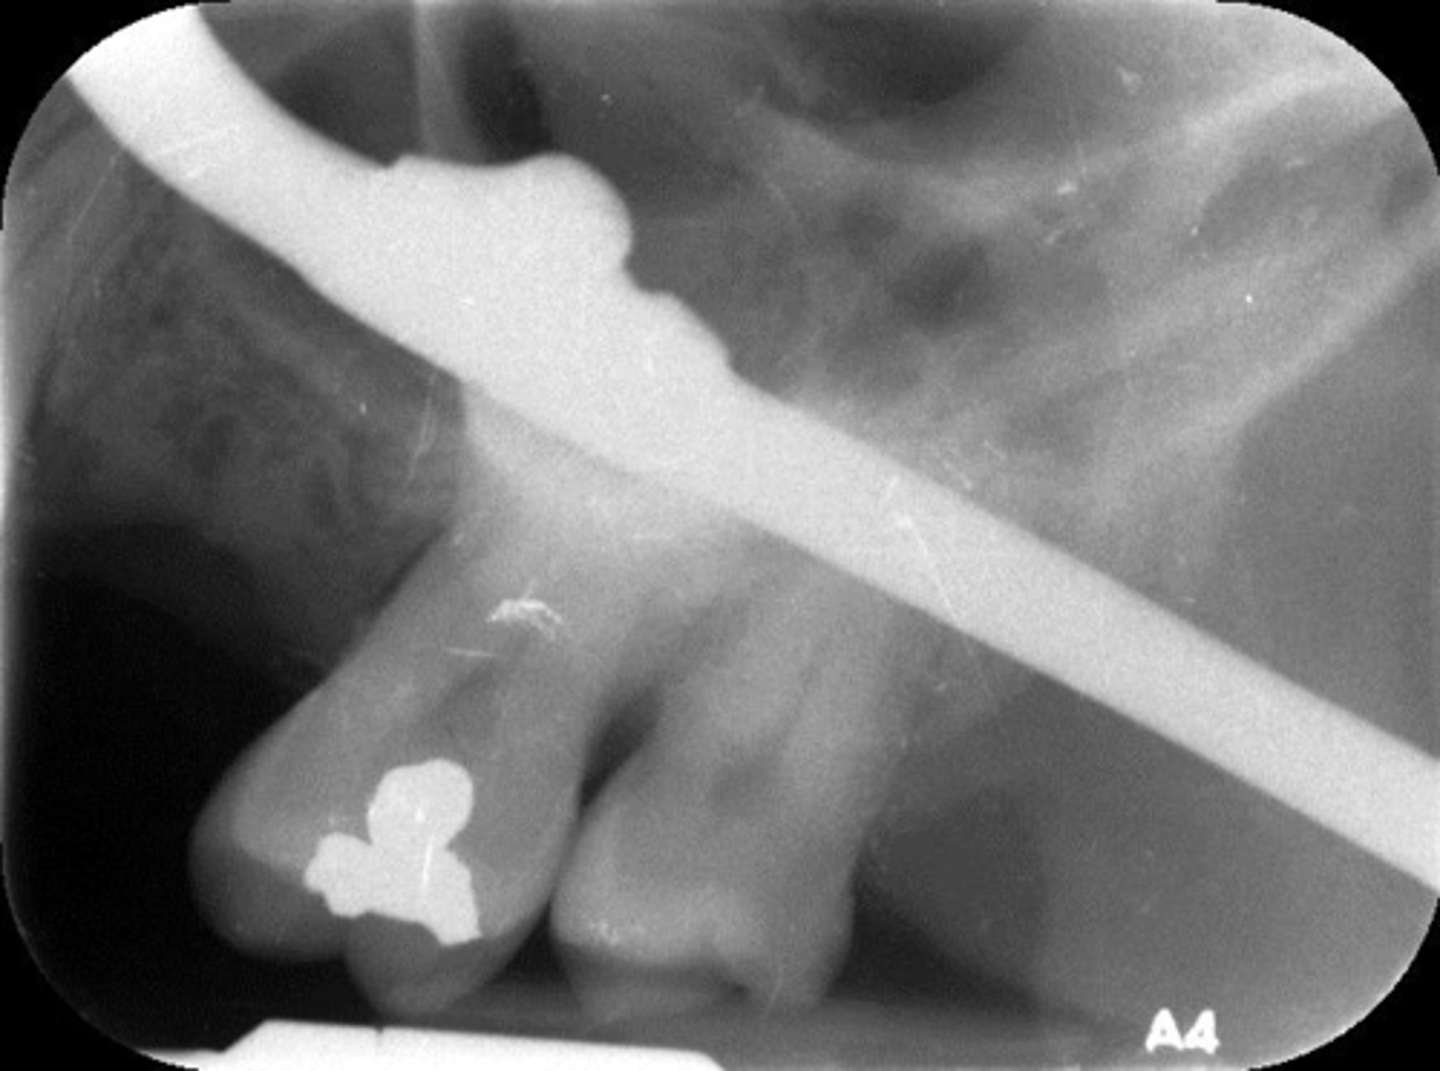

Phalangioma

Appearance-The patient's finger appears on the plate

Cause-The patient's finger was positioned in front of the plate

Correction-Make certain the patient's finger is placed behind the plate (if necessary)

What is this error?

Wrong film direction, backwards, positive angulation, wrong film size, no open contacts